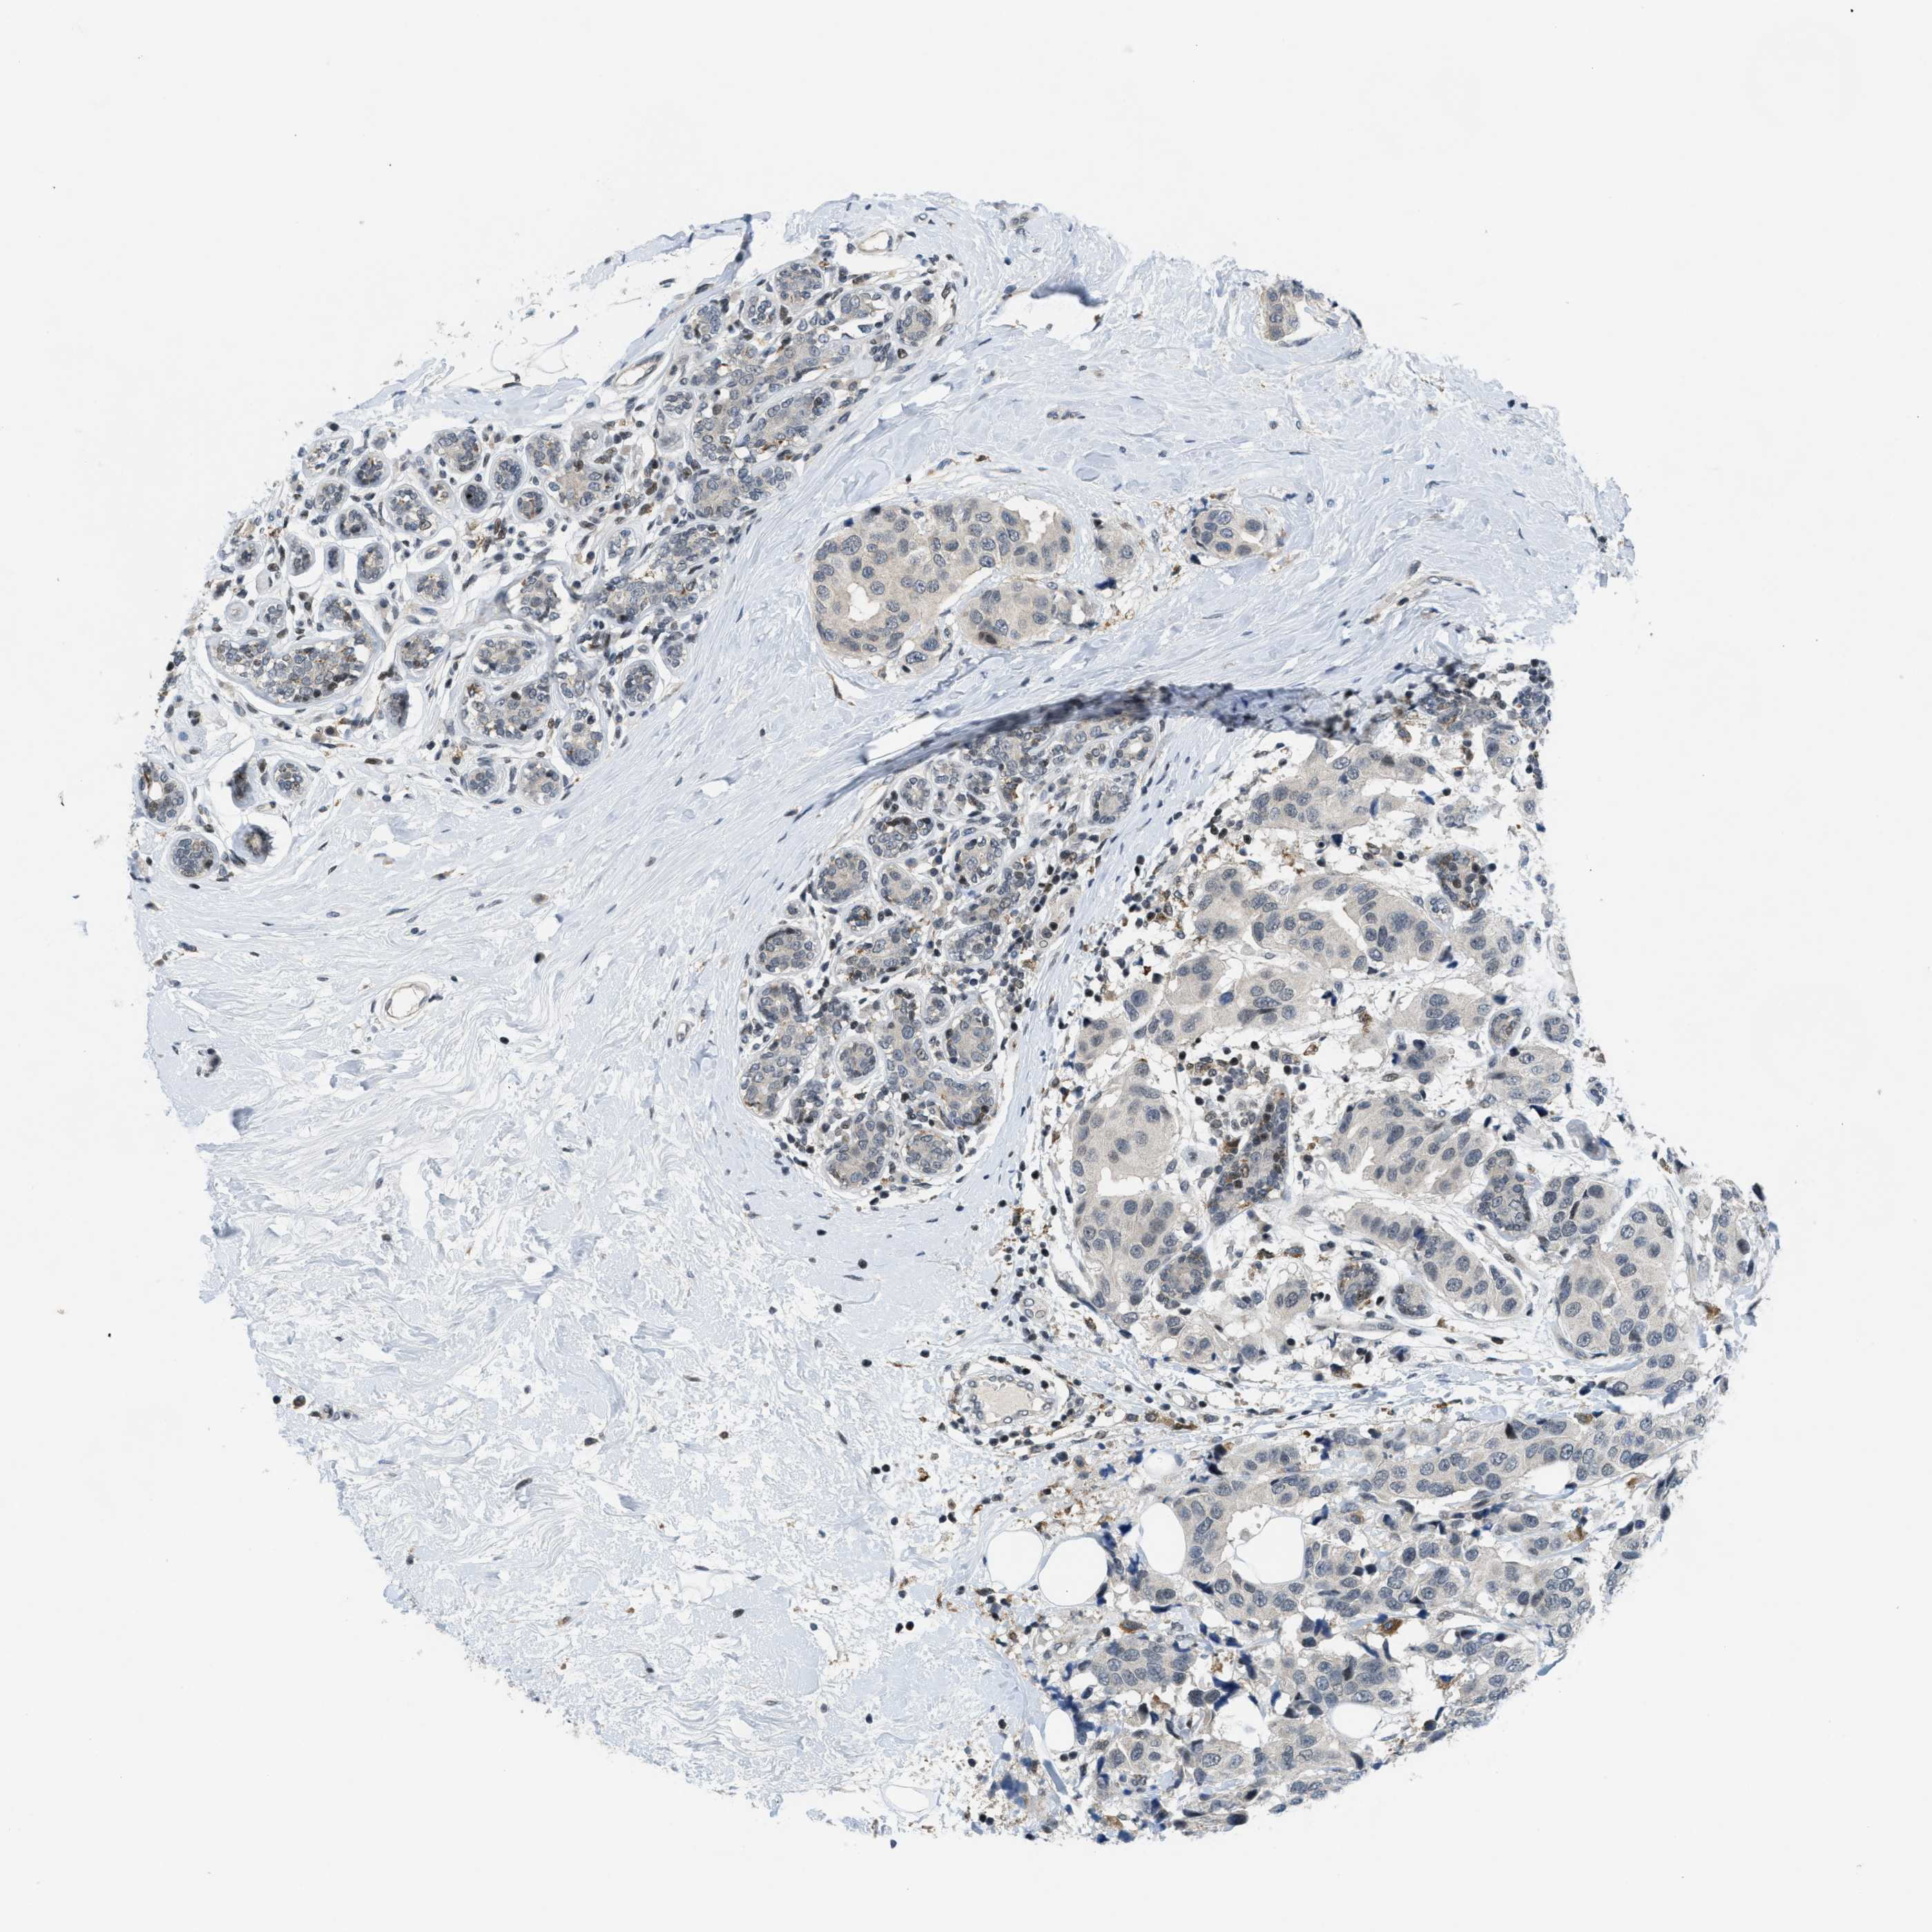

CANCER BREAST CANCER Show tissue menu

BRCA TCGA BRCA VALIDATION PROTEIN EXPRESSION

ANTIBODIES

AND

VALIDATION